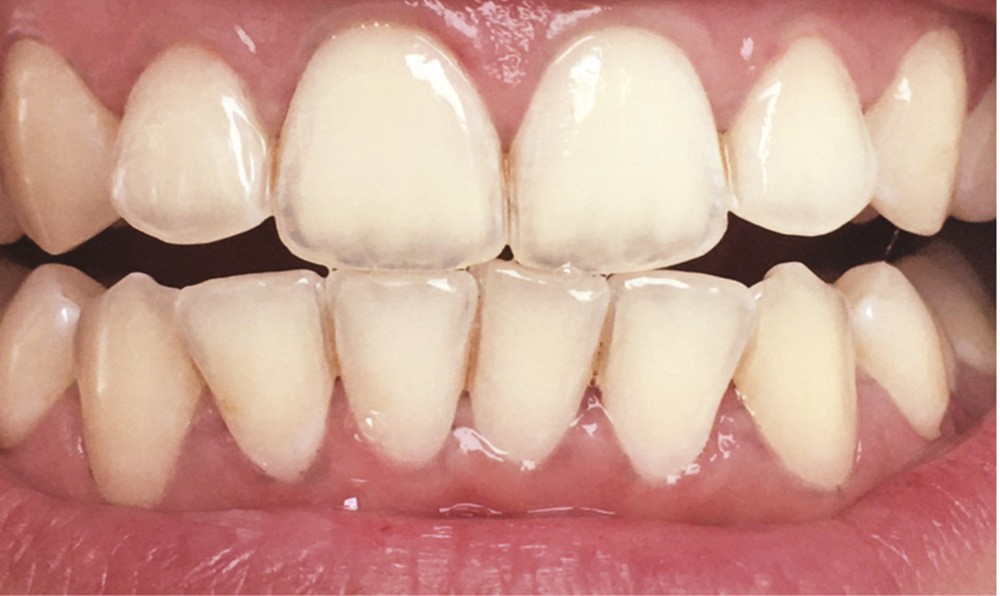

Les modifications hormonales à mettre en relation avec l’hygiène bucco-dentaire, les paramètres socio-économiques, l’âge précoce de la grossesse ainsi que l’augmentation du grignotage pourraient augmenter la prévalence des caries dentaires chez la femme enceinte. Ces patientes sont régulièrement sujettes à des envies multipliant le nombre de prises alimentaires souvent très riches en sucre. Ces apports sucrés, associés à la baisse du pH salivaire lors de la grossesse, entraînent un déséquilibre du cycle déminéralisation et de reminéralisation. Le risque carieux peut être augmenté, ainsi que la susceptibilité à l’érosion dentaire accrue par les vomissements et/ou les reflux gastro-œsophagiens [2]. L’action hormonale peut également avoir des répercussions sur les tissus parodontaux. La gingivite gravidique observée sur plus d’une femme enceinte sur deux, constitue une réponse inflammatoire de la gencive exacerbée par la présence de plaque bactérienne, et favorisée par l’augmentation des taux d’œstrogène et de progestérone [3] (fig. 1). 5 % des futures mères développeront un épulis, dont l’étiologie reste méconnue (fig. 2) [4].

Lorsque l’on consulte les sites internet, il n’existe pas de consensus quant à la technique de son utilisation. Il est généralement conseillé de frotter du citron directement sur les dents (fig. 4), ou de tremper sa brosse à dents dans du jus de citron pur et d’effectuer son brossage. Certains « tutoriels » préconisent d’utiliser ce jus ou de l’eau citronnée comme bains de bouche ! Toutes ces stratégies pour « blanchir » les dents font appel à l’acide citrique contenu dans le citron. Cet acide est l’un des composants les plus présents dans les sodas et autres boissons acides. Si les consommateurs connaissent l’effet néfaste de ces boissons sur leurs dents, ils ne font malheureusement pas le rapprochement avec le citron, un fruit, forcément bon pour la santé. Malgré un grand nombre d’études démontrant les effets nocifs érosifs du citron sur les dents définitives comme sur les dents temporaires, ces pratiques continuent à être couramment utilisées [11].

Le processus d’érosion peut être divisé en deux étapes. La première est une déminéralisation partielle. À ce stade, une reminéralisation reste possible car de l’émail déminéralisé subsiste et des ions, calciums, phosphates ou du fluor, peuvent encore s’y fixer. Quand l’utilisation d’un acide devient trop fréquente par rapport aux processus de reminéralisation, les couches superficielles d’émail fragilisées à l’occasion de la première étape sont éliminées. La perte de substance est alors irréversible (fig. 5). Après la perte de l’émail, celle de la dentine sera plus rapide du fait de sa moindre minéralisation [12]. Ces lésions peuvent entraîner des sensibilités difficiles à éradiquer et créer un déficit esthétique, à l’opposé de l’effet recherché initialement. Les effets déminéralisants de l’acide citrique, rendraient la dent plus sensible aux lésions d’abrasion et d’attrition, augmentant d’autant plus la perte de substance [14].

Le biofilm qui se reforme en quelques minutes après le brossage, protège contre l’érosion en agissant comme une barrière de diffusion ou une membrane à perméabilité sélective limitant le contact direct entre et la surface de la dent et les acides [13]. L’action de frotter du citron ou d’en imbiber sa brosse à dents réduit ou supprime l’épaisseur de la pellicule, compromettant ainsi ses propriétés protectrices. Un brossage réalisé juste avant l’application d’acide citrique est donc délétère. Il en est de même immédiatement après, car cela va éliminer l’émail préalablement déminéralisé par le citron.

Des études [15, 16] de l’état de santé bucco-dentaire tendent à montrer que la prévalence de l’érosion dentaire a augmenté dans les pays industrialisés, alors que celle des lésions carieuses a diminué de façon constante au cours de ces quarante dernières années. Ces érosions, que nous diagnostiquons de plus en plus souvent chez nos jeunes patients, pourraient devenir un problème de santé publique.